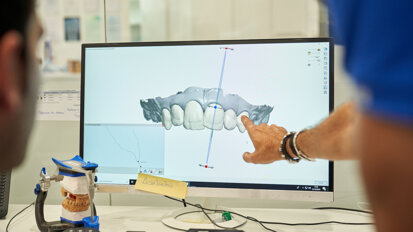

Celem niniejszego artykułu jest przedstawienie wykorzystania CBCT w postępowaniu przygotowawczym do zabiegu implantacji oraz logicznego ciągu ...